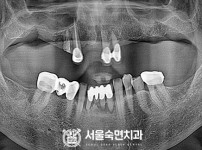

임플란트-전후사진1

임플란트-전후사진2

임플란트-전후사진3

임플란트-전후사진4

임플란트-전후사진5

임플란트-전후사진6

치과를-선택할-때-꼭-확인하세요-서울숙면치과-임플란트-전후사진